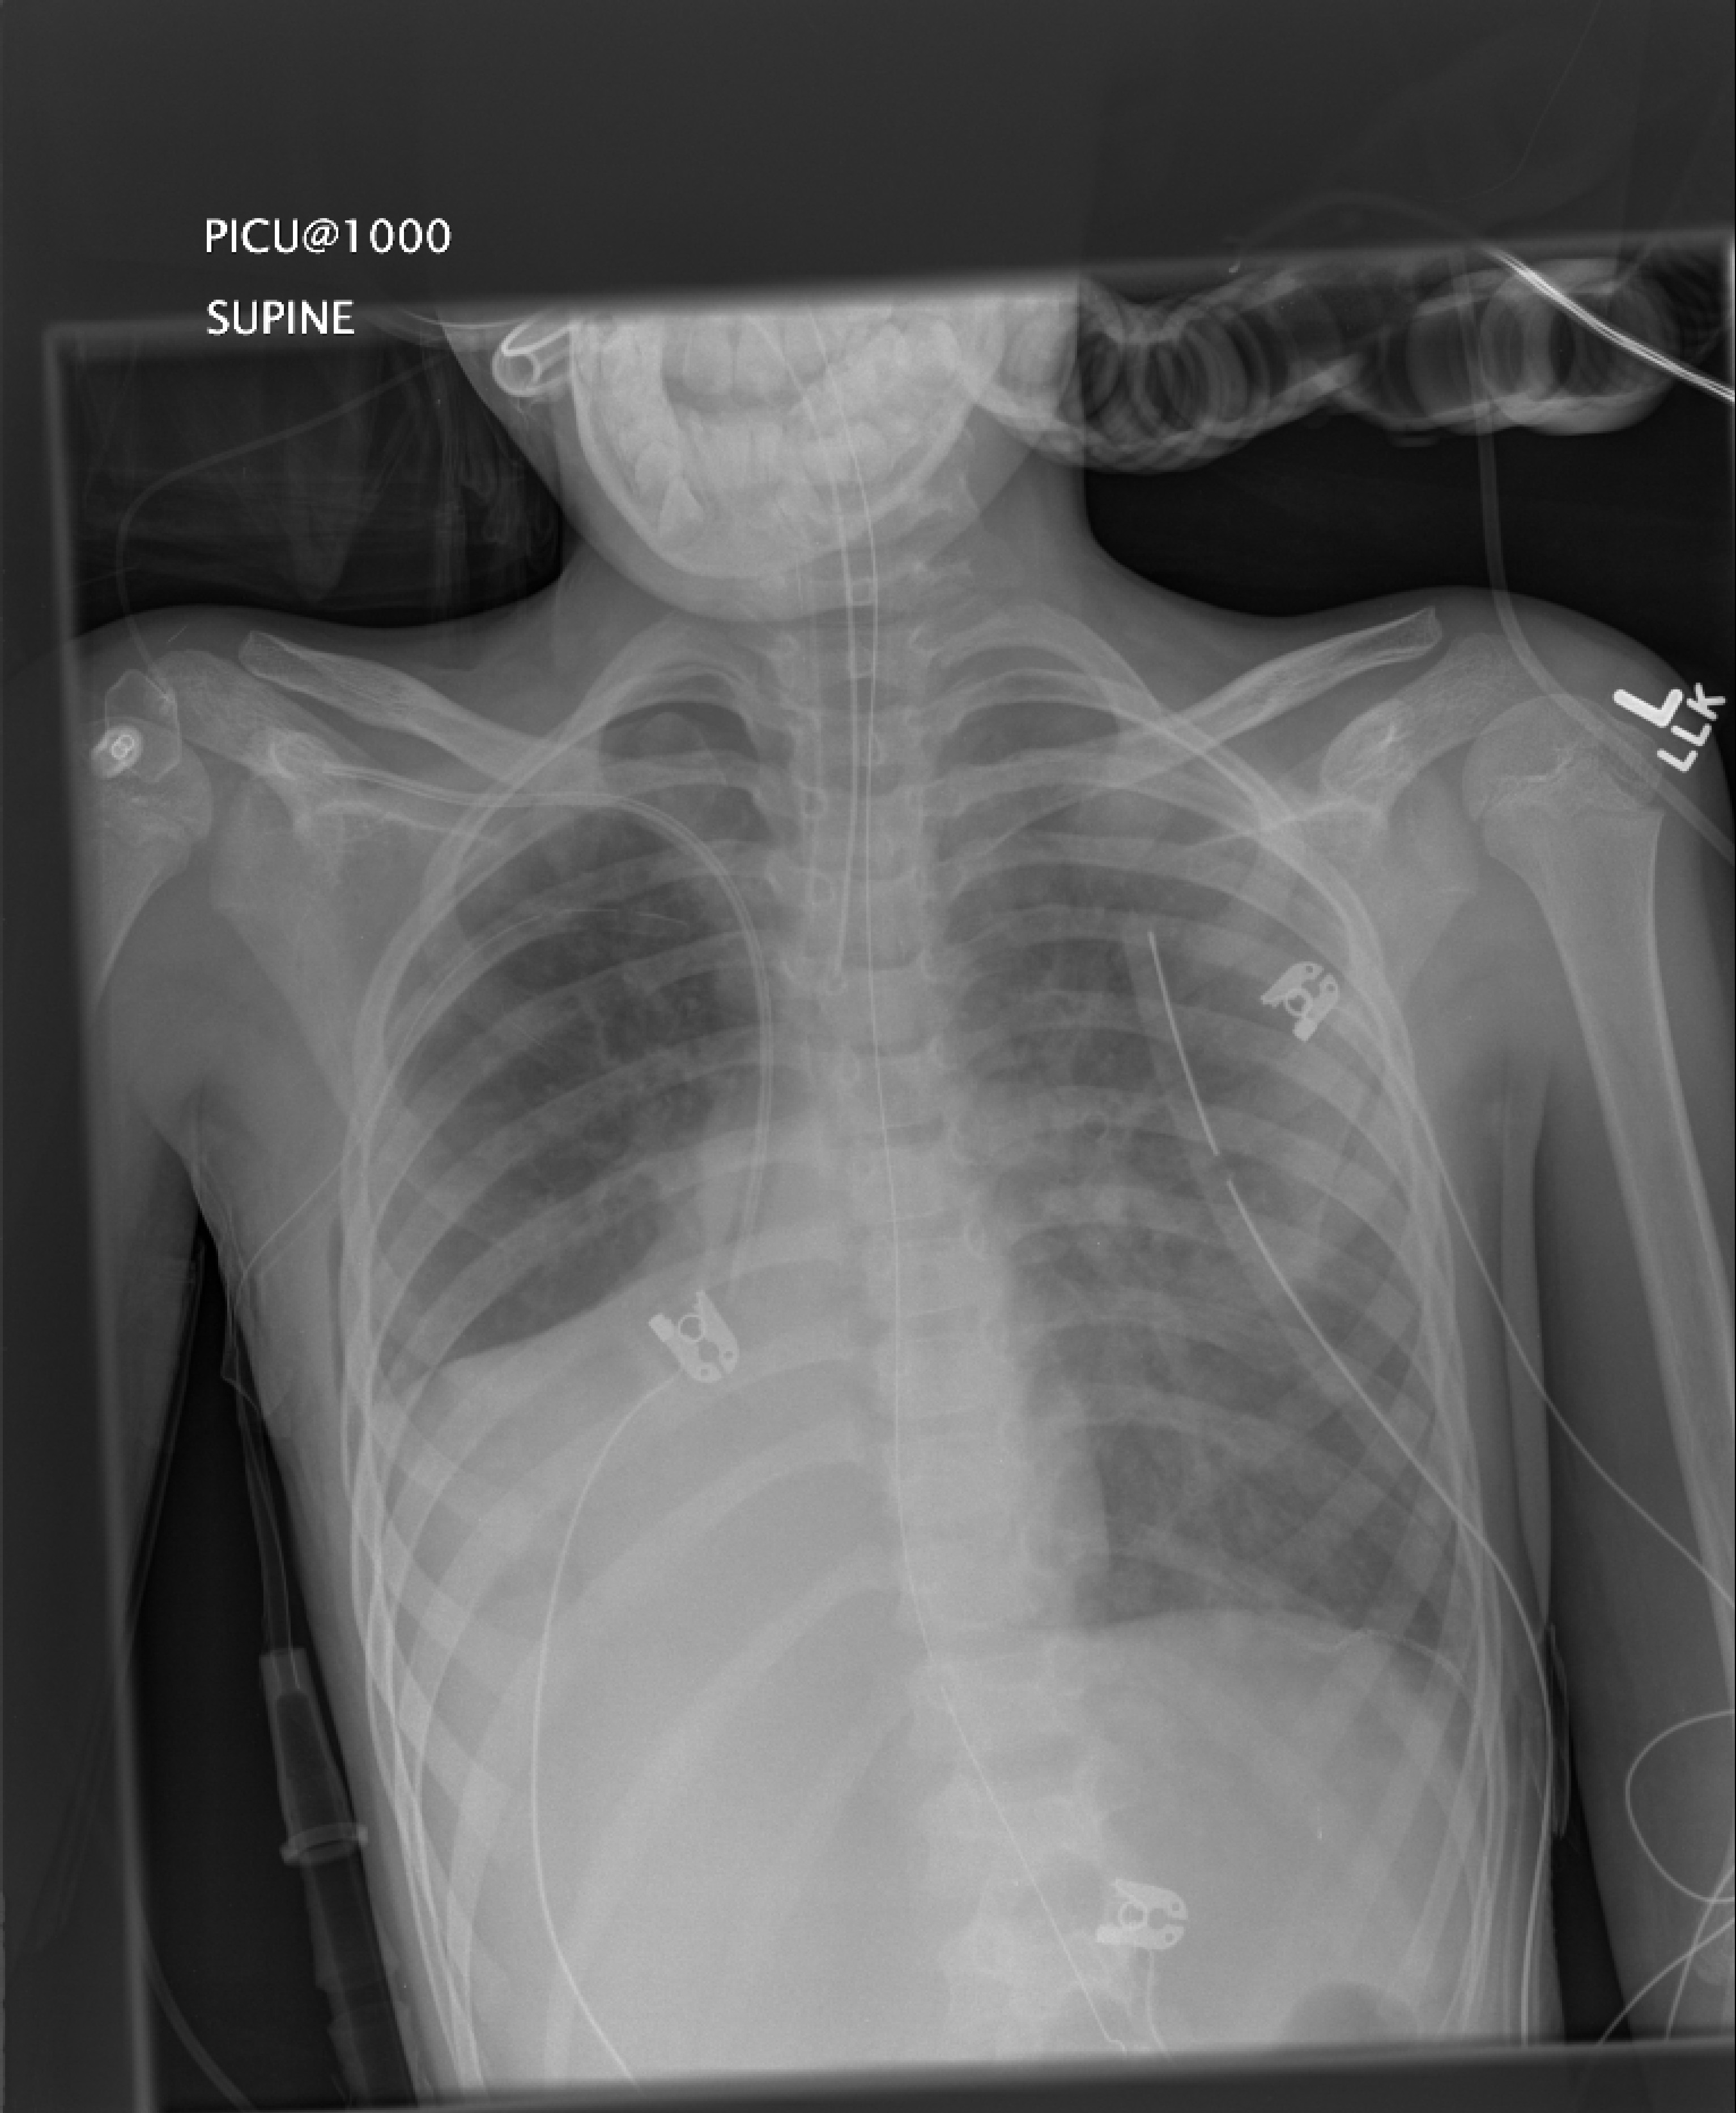

On day 20 he developed right sided atelectasis. His pressures increased to 33/15 and FiO2 to 0.85. The PICU consult the chest team regarding bronchoscopy in the morning.